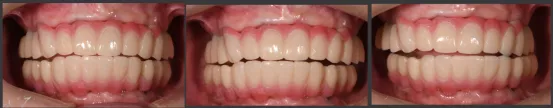

· 第二幅临时修复体戴入口内,修复效果良好,前伸侧方咬合无干扰,预留清洁通道。

· X线片显示,种植体周骨稳定性、关节髁突位置评估均无异常。

· 应用电子面弓,下颌轨迹描记测试结果显示下颌运动较对称,且稳定。

· 临时修复体仓扫后回切设计纯钛桥架。

· 制作士卓曼原厂切削纯钛桥架+氧化锆整体桥+龈瓷。

· 修复体红白美学满意,前伸侧方咬合均无干扰,前牙前突问题解决,指导患者清洁。

· 重度牙周炎伴上颌前突患者,通过数字化正侧貌美学预告,指导数字化排牙,预先制作的临时修复体,通过士卓曼360数字化序列导板成功的在术后即刻恢复患者的咬合关系。

· 应用士卓曼360数字化序列导板+预成临时修复体,能够全方位成功辅助重度牙周炎伴上颌前突患者实施即刻种植即刻修复。术后即刻获得可预期的美学和功能效果!

治疗前

治疗后